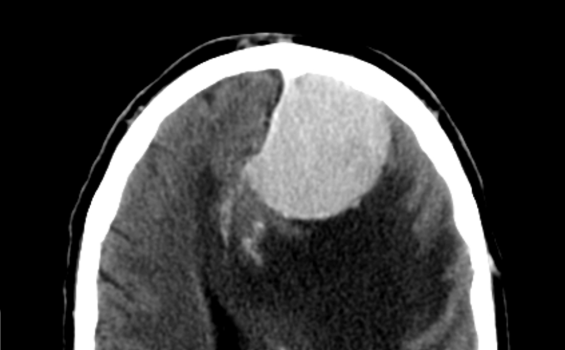

答:脑膜瘤由国际卫生组织(WHO)分级计划在形态上分为三类。尽管大多数脑膜瘤是良性或I级的,但某些亚型在治疗后复发的倾向会导致病理过程,从而导致一系列恶性疾病。脑膜瘤三级属于恶性脑膜瘤。脑膜瘤三级生存期是多少?

手术的目的是顺利切除肿瘤并获得诊断和病理分级。随后的放射治疗取决于切除范围和病理特征。携带WHO II级或III级脑膜瘤的患者复发率更高,分别在29%至52%和50%至94%之间变化。这可能部分归因于实质侵袭或残留肿瘤细胞的侵袭性。较高的复发率与总体生存率降低相关。鉴于高局部复发率,仅手术的作用通常是不足的。初步的观察研究表明,在这些情况下,放射能提高复发率和总体生存率。因此,对于II级和III级病变,放射线通常是任何治疗方案的组成部分。辐射是通过外部束源或外科手术(近距离放射治疗)过程中局部植入的放射性种子来传递的。

为了更好地了解国际卫生组织(WHO)定义的非典型和恶性脑膜瘤的预后差异以及初始手术切除等级对术后病程的影响,研究了42例非典型性脑膜瘤和29例恶性脑膜瘤。并进行长期跟进。比较了两组的长期生存率,没有复发生存率和中位复发时间。还考虑了辛普森分级的手术切除和肿瘤位置的预后意义。非典型脑膜瘤患者的5年和10年生存率分别为95%和79%,恶性脑膜瘤患者的生存率分别为64.3%和34.5%(p = 0.001)。与非典型脑膜瘤患者相比,非典型患者的没有复发生存期和中位复发时间也明显更长:分别为11.9年和2年(p = 0.001)和5年和2年(p <0.0041)。23例复发性非典型脑膜瘤中有6例(26%)变为恶性。辛普森一级切除和脑凸中的位置密切相关,被发现与整个系列中明显更好的临床过程有关(p?0.0016)。非典型脑膜瘤患者在手术切除不完全后表现优于恶性脑膜瘤(Simpson IIIII级),但差异无统计学意义。使用Cox模型进行的多变量分析表明,根治性根除(Simpson I级vs. IIIII)和组织学检查结果(非典型脑膜瘤与恶性脑膜瘤)与延长生存时间显着相关(分别为p <0.0003和p <0.0388)。总而言之,当前研究表明,对于大多数非典型脑膜瘤患者,其预后较恶性脑膜瘤患者严重,但切除不完全和复发后恶性肿瘤导致下坡的风险不可忽略(26%)。